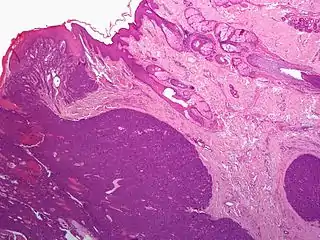

Gross pathology of a cystic nodular hidradenoma